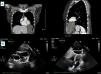

A 50-year-old woman, asymptomatic and with no relevant prior history, underwent an occupational medical examination. She was diagnosed with latent tuberculosis infection, so she was referred for a chest X-ray, which identified a mediastinal mass. She underwent a computed tomography scan in which a well-defined cystic lesion was discovered in the left costophrenic angle, about 8 cm×7 cm×10 cm in size (Figure 1A).

She was referred for a cardiology consultation to assess the hemodynamic compromise caused by the mass. A transthoracic echocardiogram (Figure 1B) confirmed the cystic lesion in the left costophrenic angle (9 cm×7 cm). It had well-defined edges and two septa inside with echolucent content, and caused mild extrinsic compression of the lateral and apical walls of the left ventricle without compromising filling of the cavity. Infiltration of the adjacent cavities was not observed, confirming the diagnosis of uncomplicated left pleuropericardial cyst.